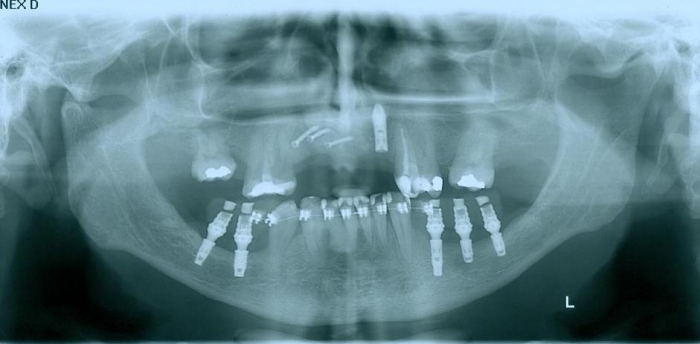

Raio - x implantes inferiores em Junho de 2011  - Clínica Cliniface

Raio - x implantes inferiores em Junho de 2011